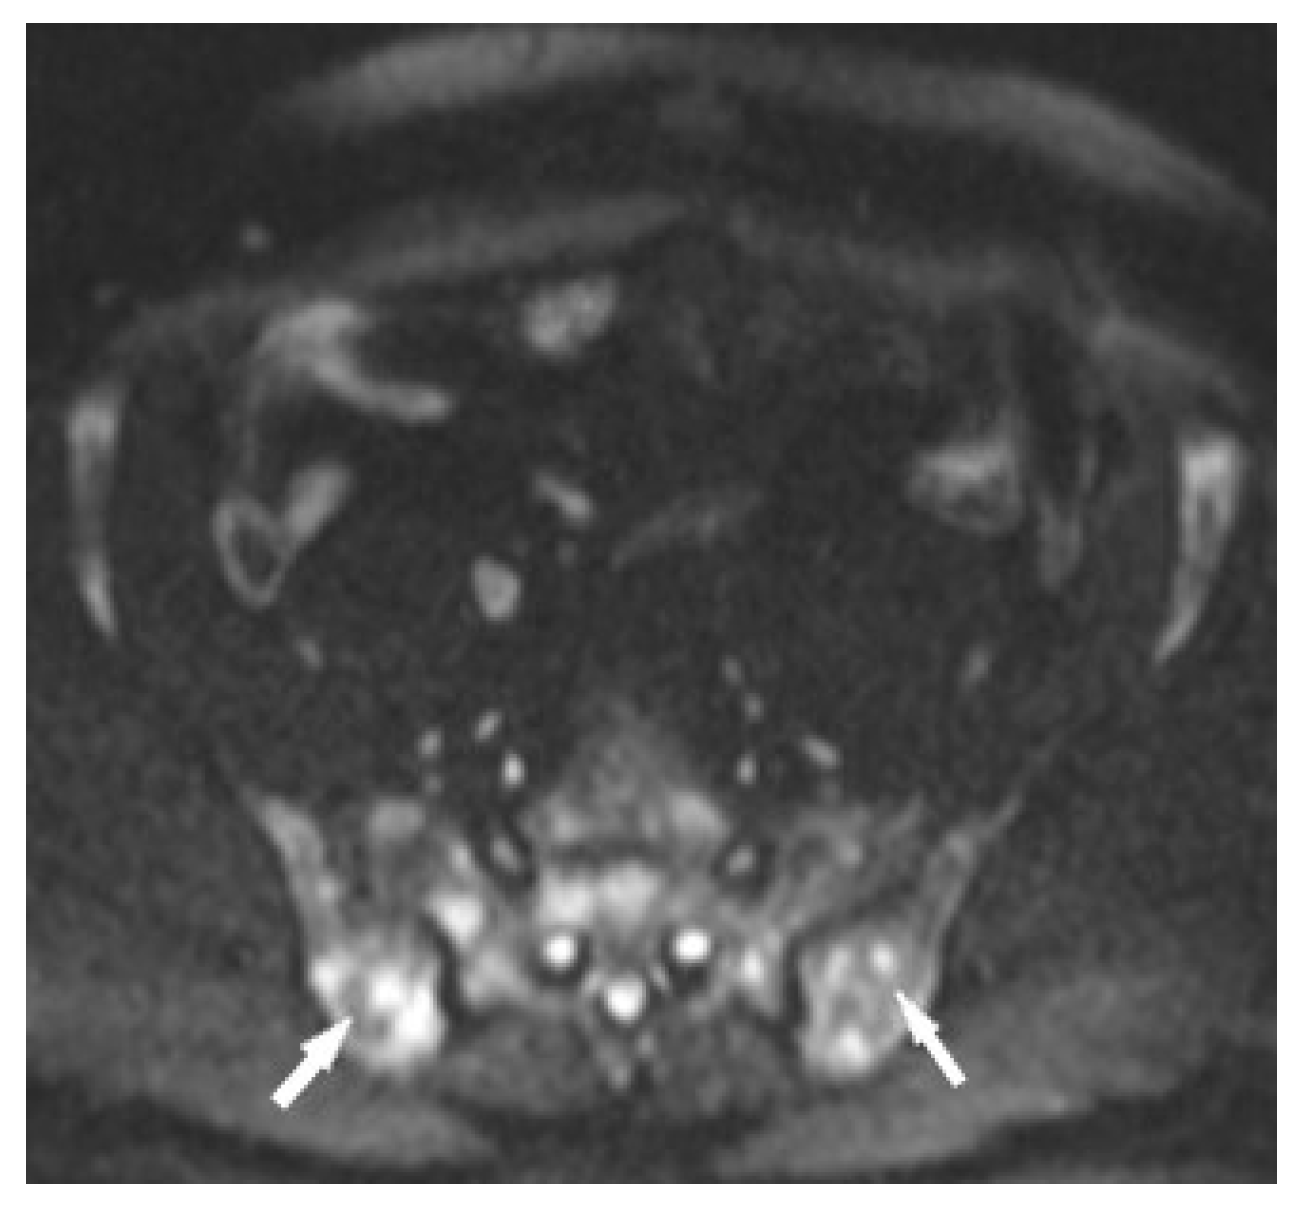

Figure 2. Lumbar spine CT, bone window. Osteosclerotic lesions (white arrows) in the L3 and S2 vertebral bodies.

Figure 8. MRI of the pelvis. T1-weighted image, coronal plane (a), T1-weighed image with fat saturation and with contrast administration (b) shows multiple hypointense bone marrow lesions (a) with contrast enhancement ((b), white arrows).

Figure 10. MRI of the pelvis, Diffusion-Weighted Imaging (DWI). Multiple bone marrow lesions with restricted diffusion (white arrows).